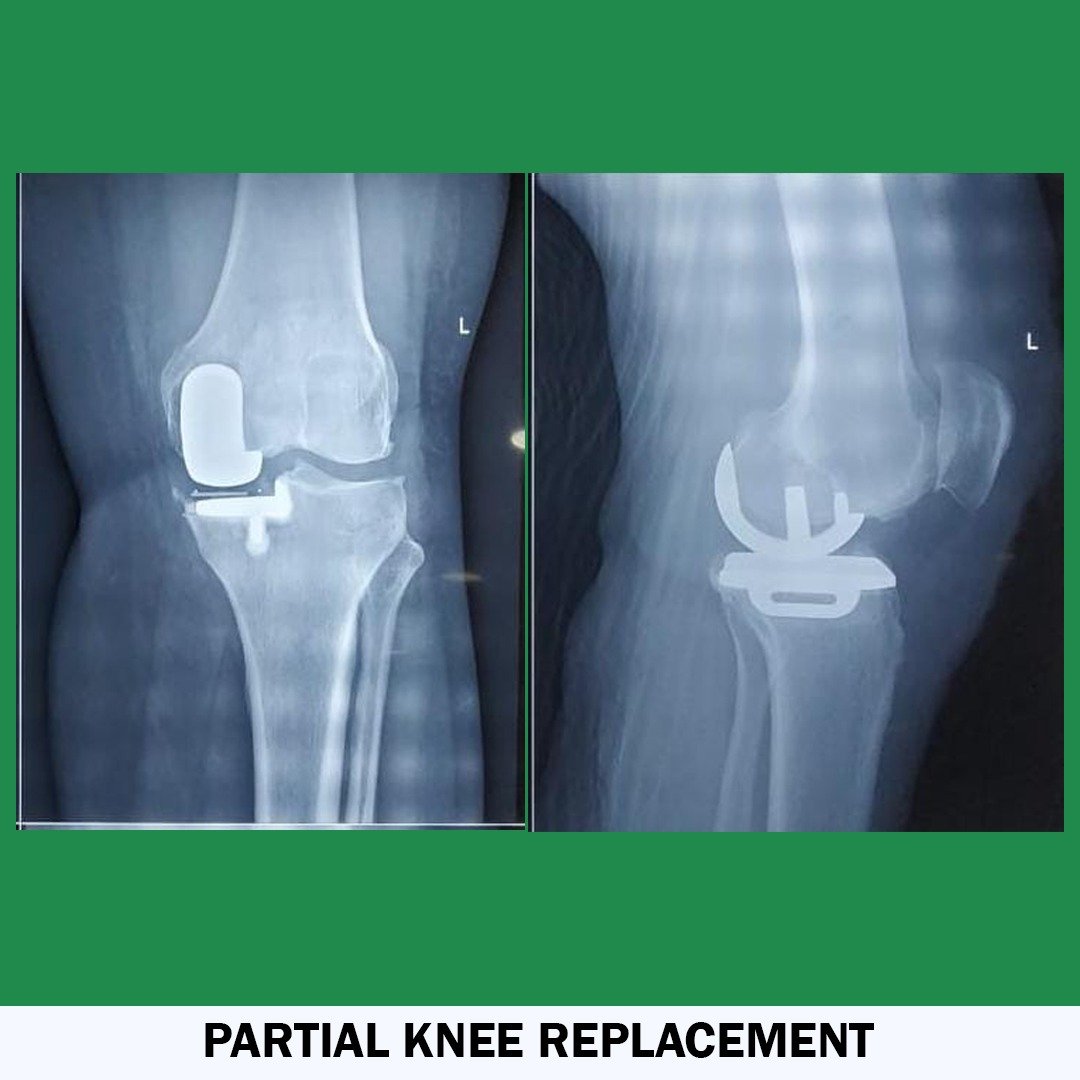

• Joint Replacement Surgeon

• Hip & Knee Reconstructive Surgeon

Knee Replacement Expert

Dr Ashok K. Sharma is a fully qualified, highly trained, and well-experienced orthopaedic surgeon in India. His Specialization is knee, hip, and shoulder replacement. He is providing the services for more than 13 years. He has performed numerous complicated Joint Replacement and Trauma Surgeries and holds the position of leading Joint Replacement and Arthroscopic surgeon in India. He has done a fellowship in Advance Knee Replacement and Arthroscopic Surgery. Dr. Sharma provides the best consultation on bone-related issues and delivers the best Surgical Outcomes. He is currently associated with Eternal Hospital and Apex Hospital Jaipur, India.